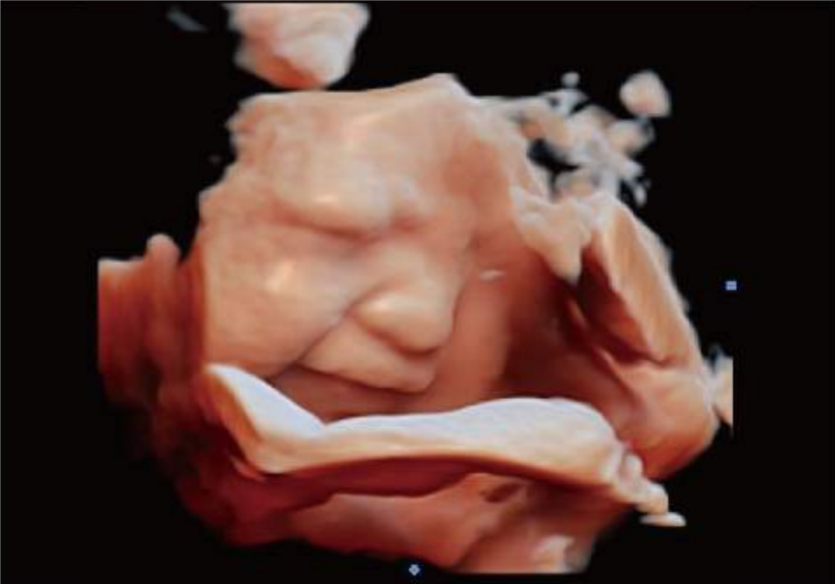

Fetal Face, Virtual HD